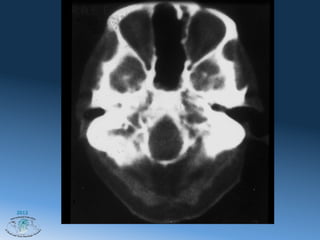

Хондросаркома

CT Scan- Axial View

режим мягких тканей и костный режим

Хондросаркома CT Scan- Axial View режим мягких тканей и костный режим 2012